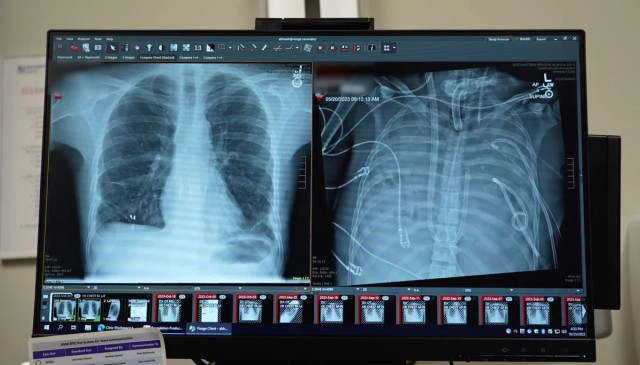

Seorang pasien diklaim berhasil bertahan hidup selama dua hari tanpa paru-paru, pada masa jeda antara pengangkatan paru-paru yang rusak parah dan kondisi tubuhnya yang cukup stabil untuk menerima transplantasi.

Dalam enam minggu berikutnya, infeksi sekunder Pseudomonas aeruginosa memicu pneumonia nekrotik. Antibiotik maupun terapi oksigen tak mampu menghentikan penurunan kondisinya. Jantung dan ginjalnya pun mulai mengalami kegagalan fungsi.

Begitu paru-paru pasien diangkat dan darahnya dialiri oksigen secara eksternal, organ-organ lain mulai menunjukkan perbaikan. Dua hari kemudian, ketika paru-paru donor tersedia, tim dokter menilai kondisinya cukup stabil untuk menjalani transplantasi. Operasi pun dilakukan.

Namun, hal itu tampak kecil kemungkinannya pada kasus ini. Pemeriksaan mendalam terhadap paru-paru yang diangkat menunjukkan jaringan parut yang begitu luas dan parah, sehingga pemulihan nyaris mustahil terjadi.